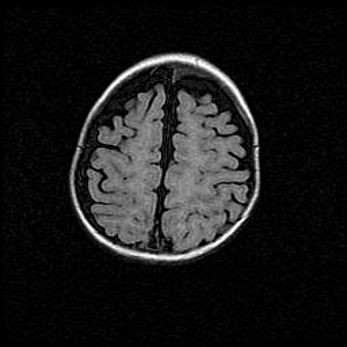

Открытая гидроцефалия.

Возраст: 9 месяцев 12 дней

Вес: 6800 г

Пол: мужской

Окружность головы: 41,5 см

Срок гестации: 28 недель

Гидроцефалия головного мозга у новорожденных имеет характерный признак: опережающий рост окружности головы приводит к визуально хорошо определяемой гидроцефальной форме сильно увеличенного в объёме черепа. Детские неврологи определяют следующие симптомы гидроцефалии у грудничков: выбухающий напряжённый родничок, частое запрокидывание головы, смещение глазных яблок к низу.